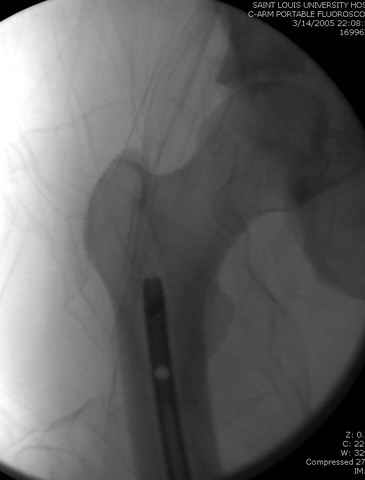

03.14.2005

больному 42, автоавария, политравма, открытая черепномозговая травма, безсознании, открытый перелом бедра, размозжение мягких тканей, дефект кожи на передней поверхности бедра около 13 см2 от ожога, компартмент синдром.

По поводу открытого перелома больной ургентно взят на ретроградное интрамедулярное штифтование, после рутинного дебрайдмента и фасциотомии на бедре и на голени.

Наблюдается службой травмы и нейрохирургии (ICP) Increased Intracranial Pressure by ventricular cateter

перелом бедра

интраоперационные